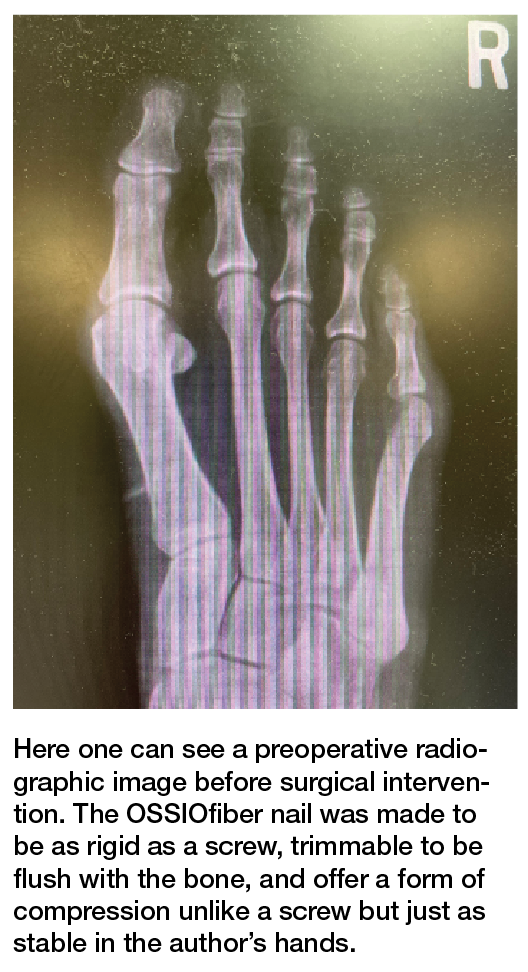

The Bio-Integrative OSSIOfiber Trimmable Fixation Nail (OSSIO) was made to be as rigid as a screw, trimmable to be flush with the bone, and offer a form of compression unlike a screw but just as stable in my hands. What was more the nail needed to require very few steps to place. Place a pin, drill over the pin, and place the nail. The nail could be placed and trimmed flush if only one cortex was drilled or it could be measured like a screw, trimmed, and inserted according to the right length for bicortical fixation options.